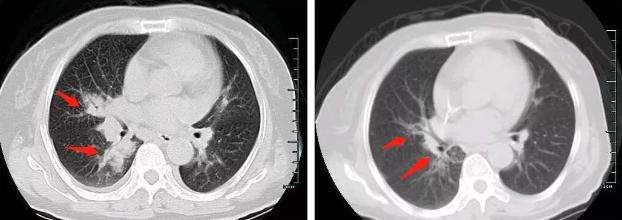

约了胸部CT扫描:

箭头所示,右肺门周围一大片高密度影,老年女性,是肺癌?肺结核?感染?

肺毛霉菌病 CT 表现无特征性,主要有实变型、多发 GGO 结节型、肿块型、空洞型。可以发生纵隔与肺门淋巴结肿大,可以出现胸腔积液。其确诊常常需要取相关病变组织做病理诊断。

这位患者比较幸运,经过积极有效地抗真菌治疗,病灶很快吸收了: